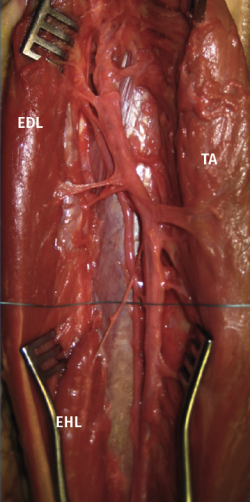

El nervio peroneo profundo (NPP), rama del nervio peroneo común (NPC), envía ramas nerviosas musculares cortas para inervar el músculo tibial anterior (TA) y extensor de los dedos largos (ELD), y suele emitir una rama motora más larga y distal, que corre inferiormente a lo largo del periostio del peroné hasta que alcanza el EHL (Figura 1)(1).

Figura 1. Véase la rama motora dependiente del nervio peroneo profundo, más larga, delgada y distal respecto a las otras, que discurre inferiormente hasta alcanzar el vientre muscular del EHL. EDL: extensor de los dedos largos; EHL: extensor largo del dedo gordo; TA: tibial anterior.